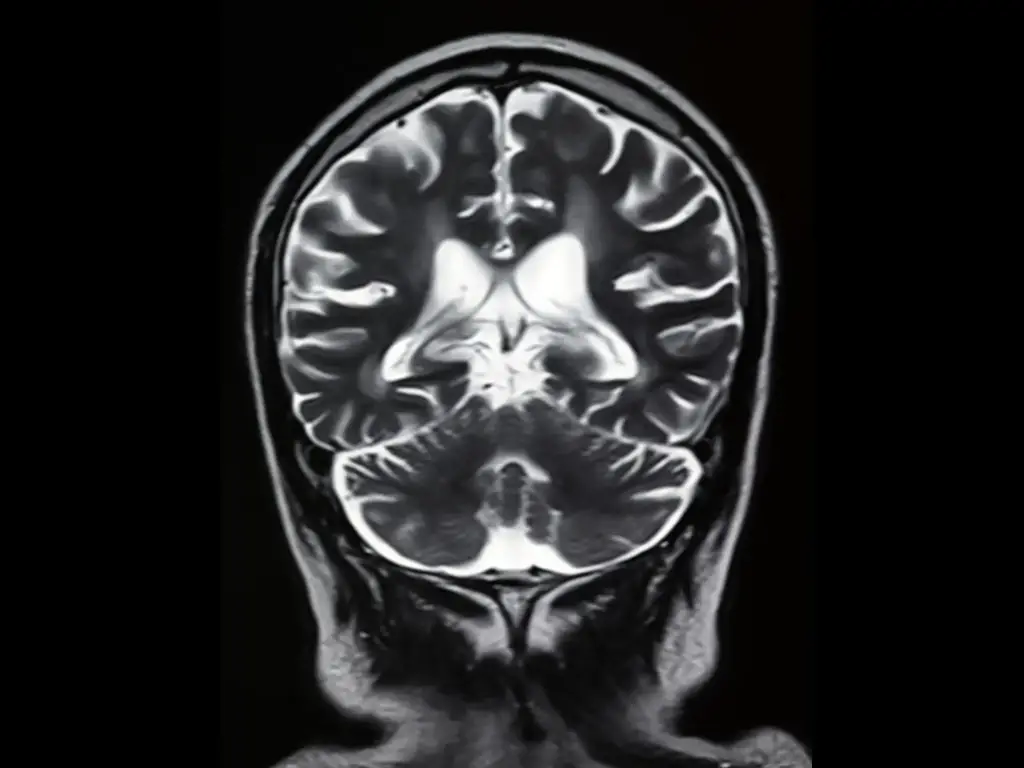

《了解你孩子的大脑》使用基本的神经科学来解释小孩子在生命的最初几年是如何思考、感受和表现的。该书旨在帮助父母解决常见的育儿问题,如发脾气,并促进其后代的健康智力和情绪发展。

书中概述的每个育儿建议主题都与一个特定的大脑区域以及该区域在儿童中的发展情况有关。毕尔巴鄂博士说,幼儿的行为是由脑干(爬行动物脑)和边缘系统(古哺乳动物或情绪脑)控制的--而不是理性脑。